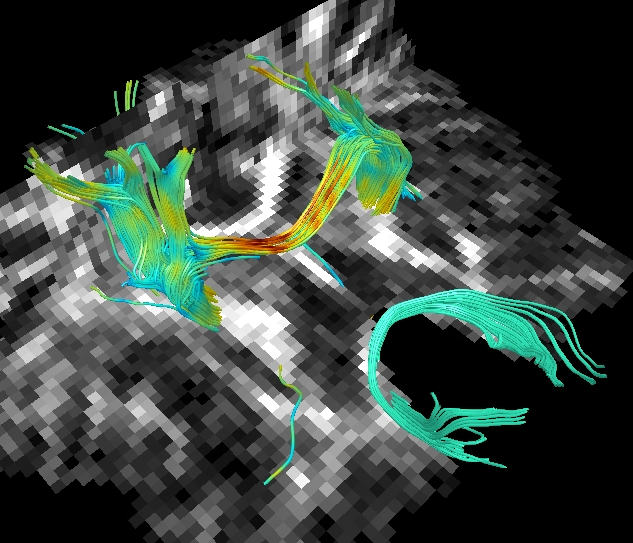

| 9.DWI(拡散画像)の解析 | 拡散テンソル画像とファイバー・トラッキング | ![]() |